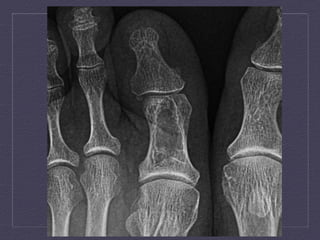

Enchondroma     Benign  medullary  car:laginous  neoplasm     Childhood  to  early  adulthood  (10-­‐30  y.o)     Arise  from  chondrocytes  composed  of  mature  hyaline   car:lage     X-­‐Ray  and  CT:  1-­‐2  cm  non-­‐aggressive  ly:c  lesions,  endosteal   scalloping,  chondroid  calcifica:on,  periosteal  reac:on  (-­‐),sof   :ssue  mass  (-­‐)     MRI:  Intermediate-­‐low  signal  T1WI,  high  signal  T2WI     Treatment  and  Prognosis:  No  treatment  à  cure`age  and   bone  grafing